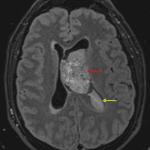

- Mildly FLAIR hyperintense intraventricular mass in the body of the left lateral ventricle measuring 4.3 x 3.7 cm in axial dimensions with heterogeneous corresponding enhancement and restricted diffusion

- The mass broadly contacts the septum pellucidum

- Associated mass effect with 1.5 cm left-to-right midline shift

- Crowding of the foramen of Monro with enlargement of the left greater than right lateral ventricles, consistent with obstructive hydrocephalus

- T1 isointense, FLAIR hyperintense material alongside the mass and layering in the left greater than right lateral ventricles and third ventricle, most likely representing hemorrhage (likely related to ventricular drain placement)

- Left frontal approach external ventricular drain terminates alongside or within the intraventricular mass. Mild edema along the parenchymal course of the catheter

Central neurocytoma